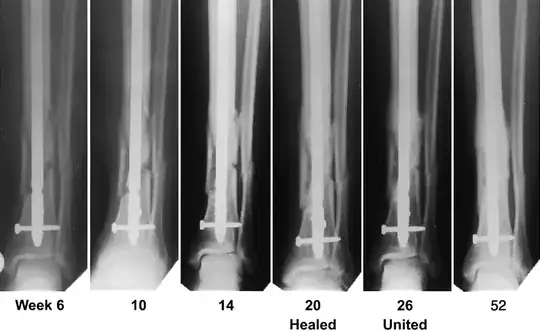

This is a series of radiographs of a more serious tibial-fibular fracture (tib-fib fx for short) at different time periods:

There was an extensive repair done on this tib-fib fx, but looking at the week 10 fracture, you will see that, like yours, it doesn't look much different from the day 1 radiograph. What you can see if you look carefully is a kind of softening of the edges of the fractures. This is due to bone remodeling and callus formation.

The callus is barely visible in this series until week 14 (the image isn't very high quality), and is becoming obvious by week 20.

Image obtained from Recombinant Human Bone Morphogenetic Protein-2 for Treatment of Open Tibial Fractures